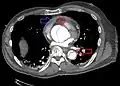

Computed tomography angiography is a fast, non-invasive test that gives an accurate three-dimensional view of the aorta. These images are produced by taking rapid, thin-cut slices of the chest and abdomen, and combining them in the computer to create cross-sectional slices. To delineate the aorta to the accuracy necessary to make the proper diagnosis, an iodinated contrast material is injected into a peripheral vein. Contrast is injected and the scan performed using a bolus tracking method. This type of scan is timed to injection to capture the contrast as it enters the aorta. The scan then follows the contrast as it flows through the vessel. It has a sensitivity of 96 to 100% and a specificity of 96 to 100%. Disadvantages include the need for iodinated contrast material and the inability to diagnose the site of the intimal tear.

Chest CT with descending (type B Stanford) aortic dissection (red circle)